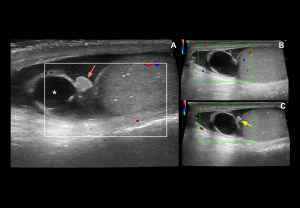

Doppler findings:

- Degree of torsion:

- Complete (≥360°): Usually absent intratesticular flow.

- Partial (<360°): Residual intratesticular flow may be detectable.

- Spectral Doppler: Increased resistive index (RI) and possible diastolic flow reversal, whirlpool sign of spermatic cord

- Late (>24 h): Periscrotal hyperaemia reflects inflammation.